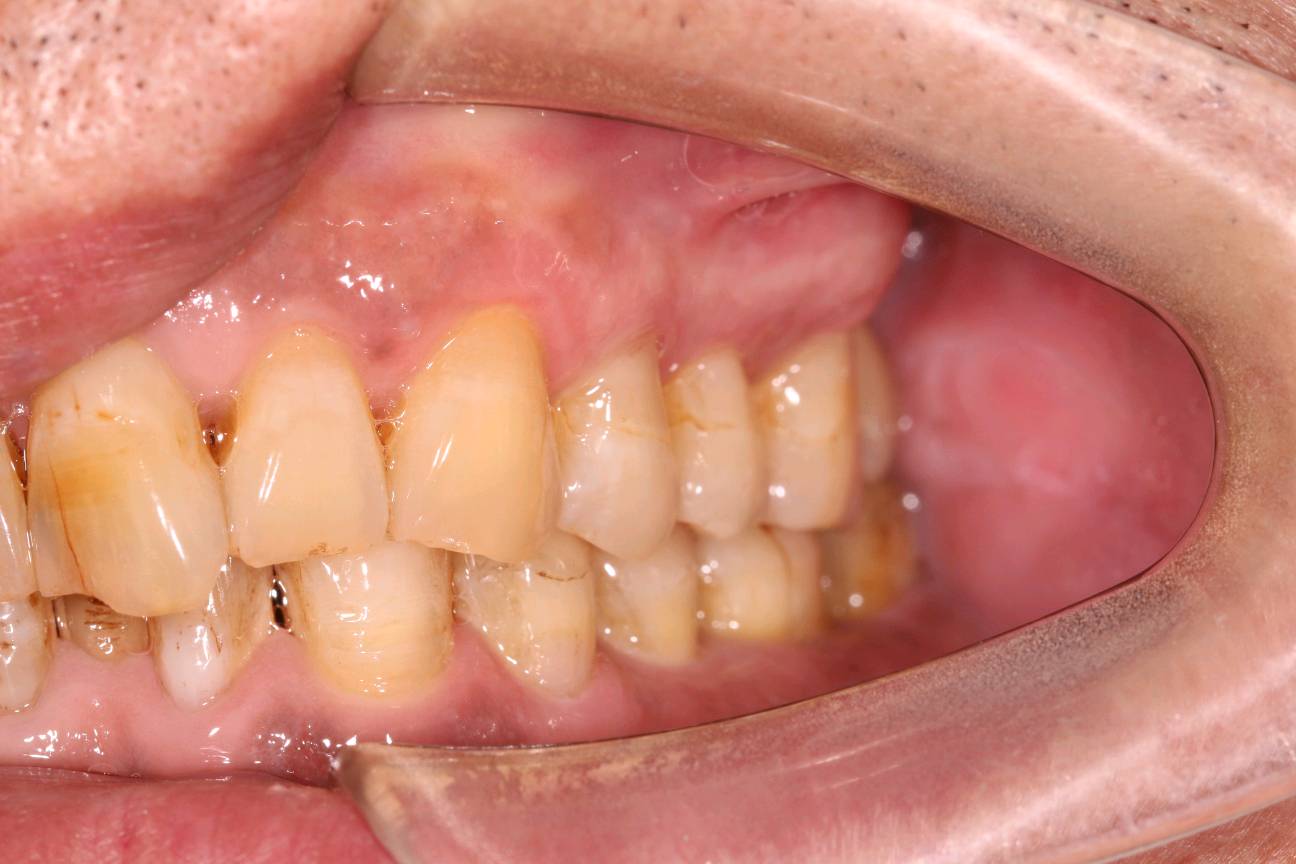

患者是成功人士,平时非常忙碌,忽略了口腔健康,直到有一天无法咀嚼食物后才想到要治疗牙齿,我们为他摄了CBCT,发现有重度牙周病,上合双侧7自然脱落,左上8,III度松动,并近中倾斜移位,对合牙严重伸长,还有其他牙齿疾患,需要综合治疗;经过牙周病治疗、上合窦骨增量、上合种植修复、拔牙、截冠、根管治疗、桩冠、高嵌体修复等!时间长达一年,终于恢复了正常牙列!可以享受食物的美好!